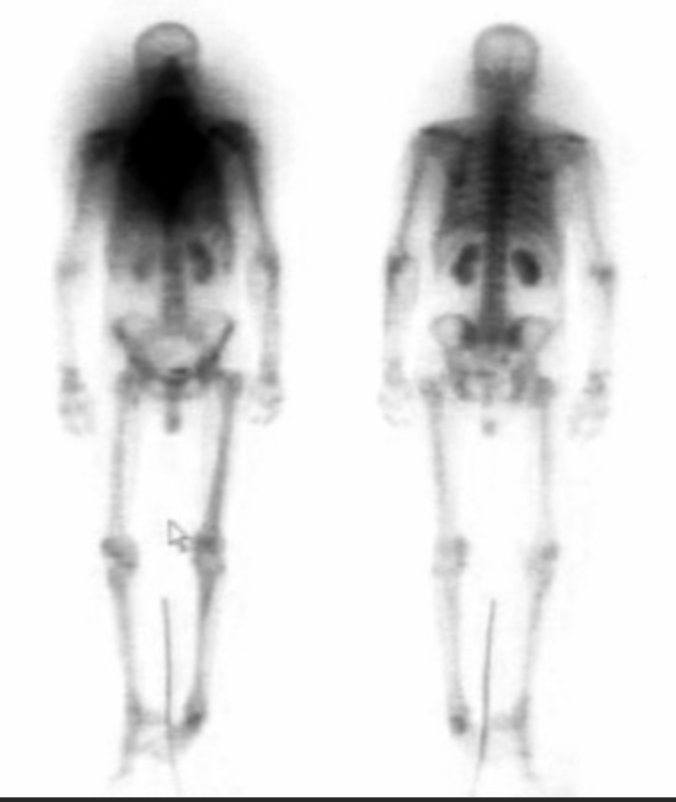

Normal kid

• Uptake in epiphysis in kids - normal

• Kid - we know because growth plates light up